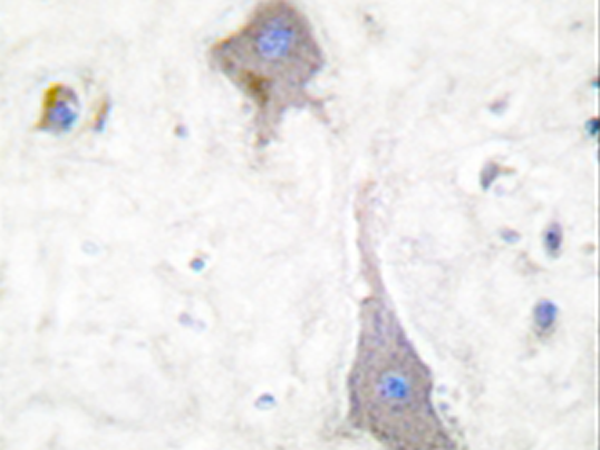

IHC positive control: |

Human brain tissue |